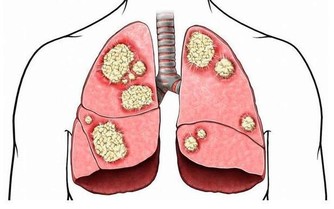

5、咯血

肺結核,支氣管擴張導致咯血患者,緊張的胸腔,腹腔壓力突然升高,血管壁破裂,造成大咯血。